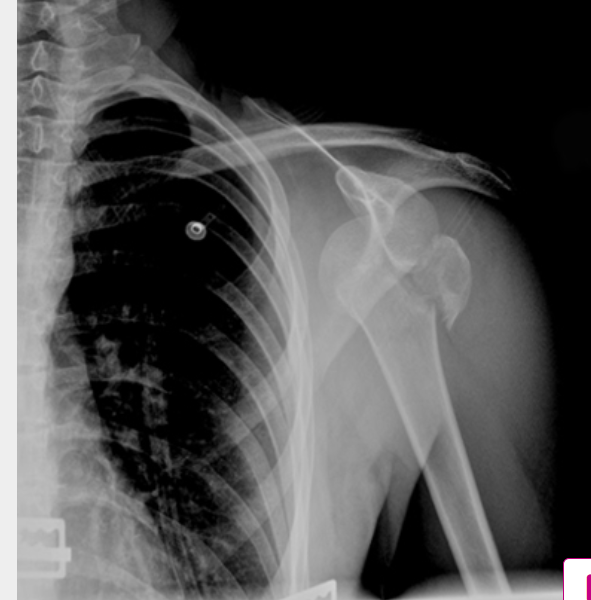

anteroinferior dislocation (AP XR)